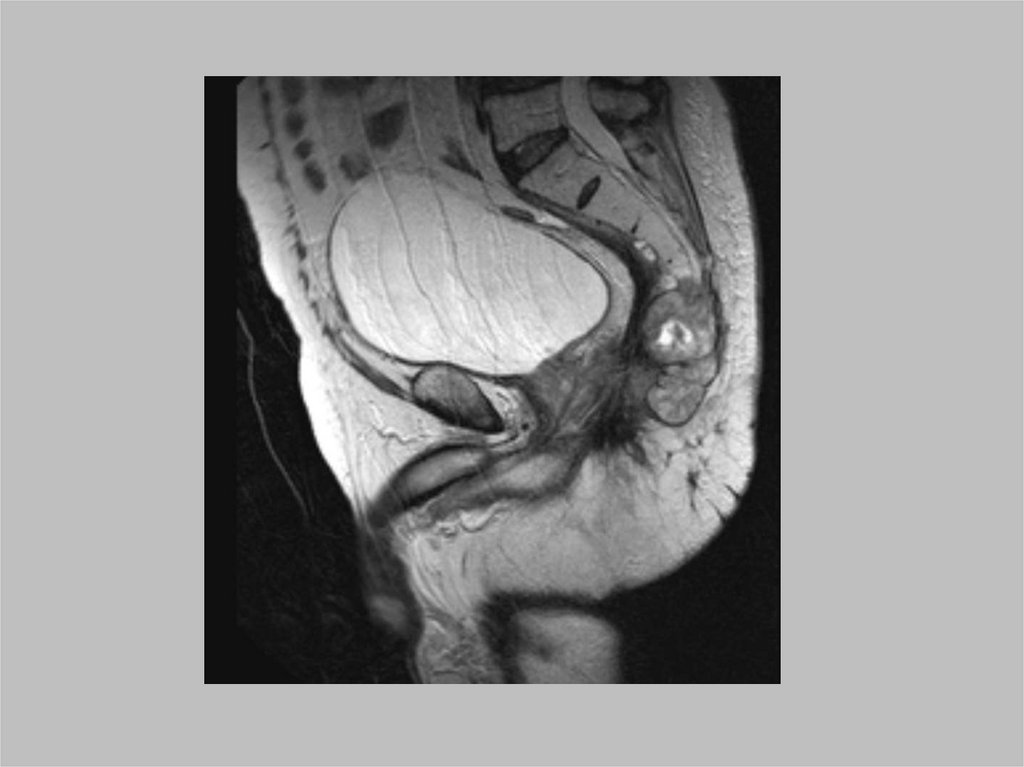

Симфизит